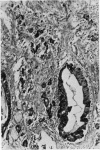

Ten cases of mucocele of the vermiform appendix are described. Eight cases were of mucinous cystadenoma of the appendix and six cases showed acute inflammation. Two of the six cases showed pseudoinvasion of the appendix and in a further case the appendix had perforated with extrusion of a misplaced neoplasm. Two cases were of mucinous cystadenocarcinoma and one of these was diagnosed as `pseudomyxoma peritonei'. `Pseudomyxoma peritonei' is a misnomer and is caused by dissemination of a mucinous cystadenocarcinoma within the peritoneal cavity. The special problems of histological diagnosis are discussed.